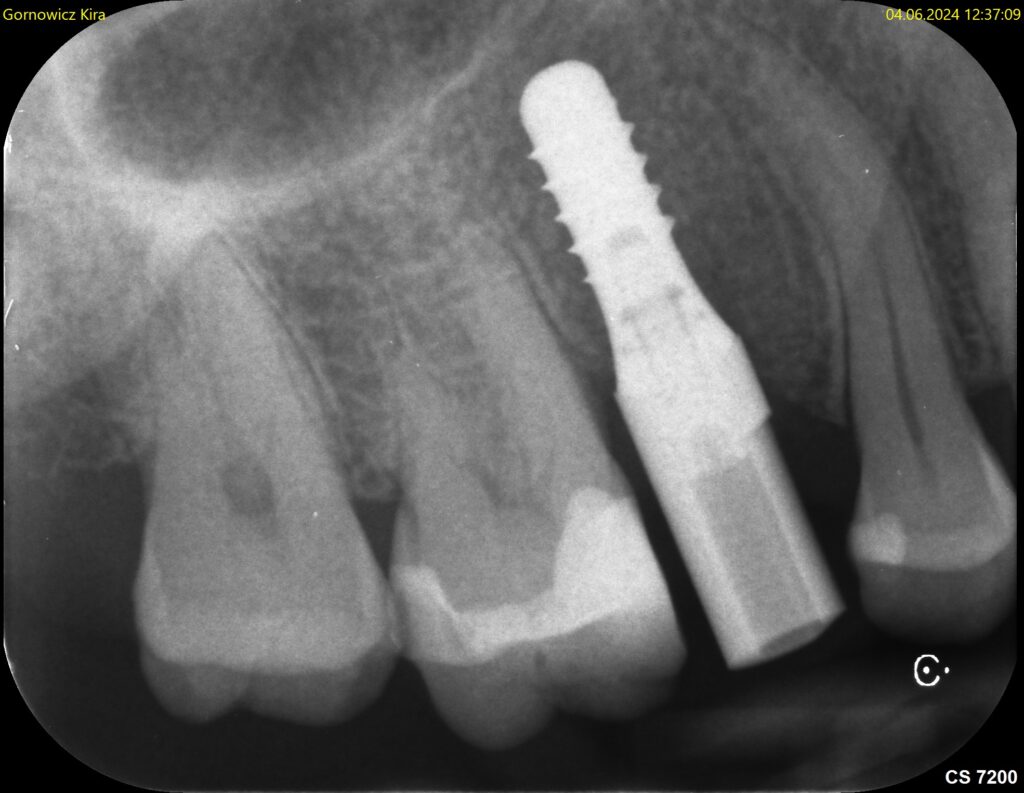

Ein Scanabutment ist eine Funktionselement, das in ein Implantat eingeschraubt wird, um die digitale Übertragung der Implantatposition im Kiefer für das Labor über einen optischen Scan zu ermöglichen.

Da zwischen Scanabutment und Implantat nur eine korrekte Passung möglich ist (Schlüssel-Schloss), kann der im Scan (optischer Abdruck) aufgezeichnete Scan-Pfosten auch nur die tatsächlich Implantatposition wiedergeben.